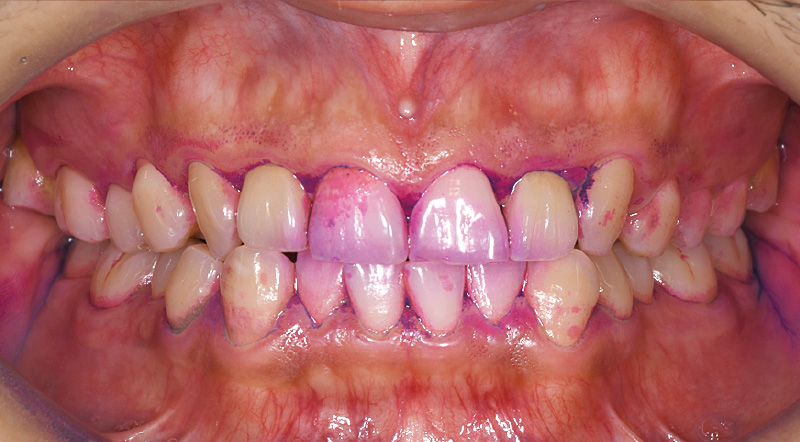

●症例1:50代男性

月に一度来院し、プロフェッショナルケアを継続されていました。セルフケアについては、どれだけ指導しても手磨きではモチベーションが上がらず磨き残しが多い状態で、1日40本の喫煙による着色も見られました。そんな中、インプラント治療後にインプラント周囲炎のリスクが高まり、セルフケアが不可欠になったことから、「ソニッケアー6100プロフェッショナル」(以下:ソニッケアー6100)の導入を提案。「歯磨きが楽になる」という利点を伝えながら使い方を指導したところ、思いのほか前向きに受け入れてくださり、導入後2週間でプラークや着色が大幅に減少するという顕著な改善がありました。患者さん自身も効果を実感し、セルフケアに対するモチベーションもぐんと上がった様子でした。

![[写真] 「ソニッケアー6100」使用前。写真右:使用から2週間後の状態](/academic/dentalmagazine/wp-content/uploads/sites/2/2026/04//196-12_photo06.jpg)

症例1-6 写真左:「ソニッケアー6100」使用前。写真右:使用から2週間後の状態。着色が大幅に減少していることがわかる。